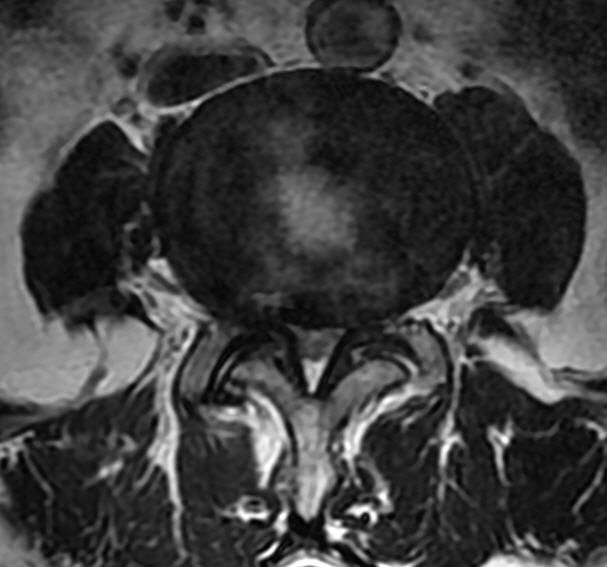

MRI

可提供腰椎管的矢状面、冠状面和轴位横断面上的影像。椎管狭窄以T2加权像显示较好,脑脊液为高信号,产生所谓“脊髓造影”的效果,而骨质增生,骨赘、间盘均为低信号,能清晰地显示椎管狭窄,以及对脊髓的压迫情况。但对肥大的黄韧带、骨质增生等的判断则不如较高清晰度CT扫描。

腰椎正常MRI解剖。

腰椎管狭窄MRI表现。